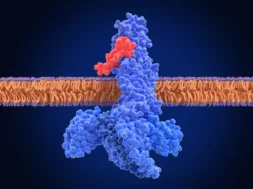

Το παιδί ήταν εμβολιασμένο , όπως και το δίδυμο αδελφάκι του, που νοσηλεύεται ακόμα στο Νοσοκομείο του Βόλου. Τα εργαστηρικαά ευρήματα είναι ίδια και για το δεύτερο παιδί . Τα παιδιά, σύμφωνα με τις ίδιες πληροφορίες, είχαν εμβολιαστεί με συζευγμένο πνευμονιοκοκκικό εμβόλιο που ενδείκνυται για την προστασία βρεφών και νηπίων από τη διεισδυτική πνευμονιοκοκκική νόσο, την πνευμονία και την οξεία μέση ωτίτιδα που προκαλούνται από τους 13 ορότυπους που περιλαμβάνονται στο εμβόλιο.

“Υπάρχουν σπάνια στελέχη, σπάνιες περιπτώσεις, που δεν καλύπτονται από το εμβόλιο”, δήλωσαν οι γιατροί στα gegonota.news.